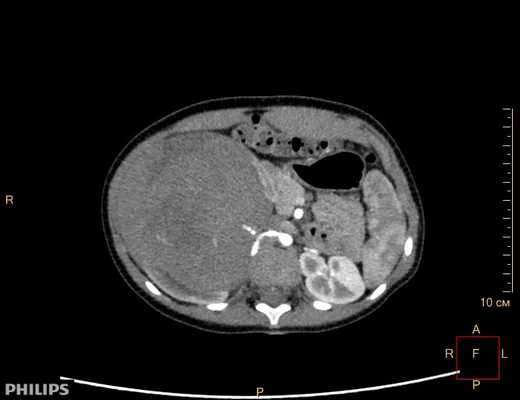

- Томографическое исследование. КТ почки контрастным усилением позволяет обнаружить рак почки любого размера, установить его структуру и локализацию, глубину прорастания паренхимы, инфильтрацию паранефральной клетчатки, опухолевый тромбоз почечной и нижней полой вен. При наличии соответствующих симптомов проводится КТ органов брюшной полости, забрюшинного пространства, костей, легких и головного мозга с целью выявления метастазов.